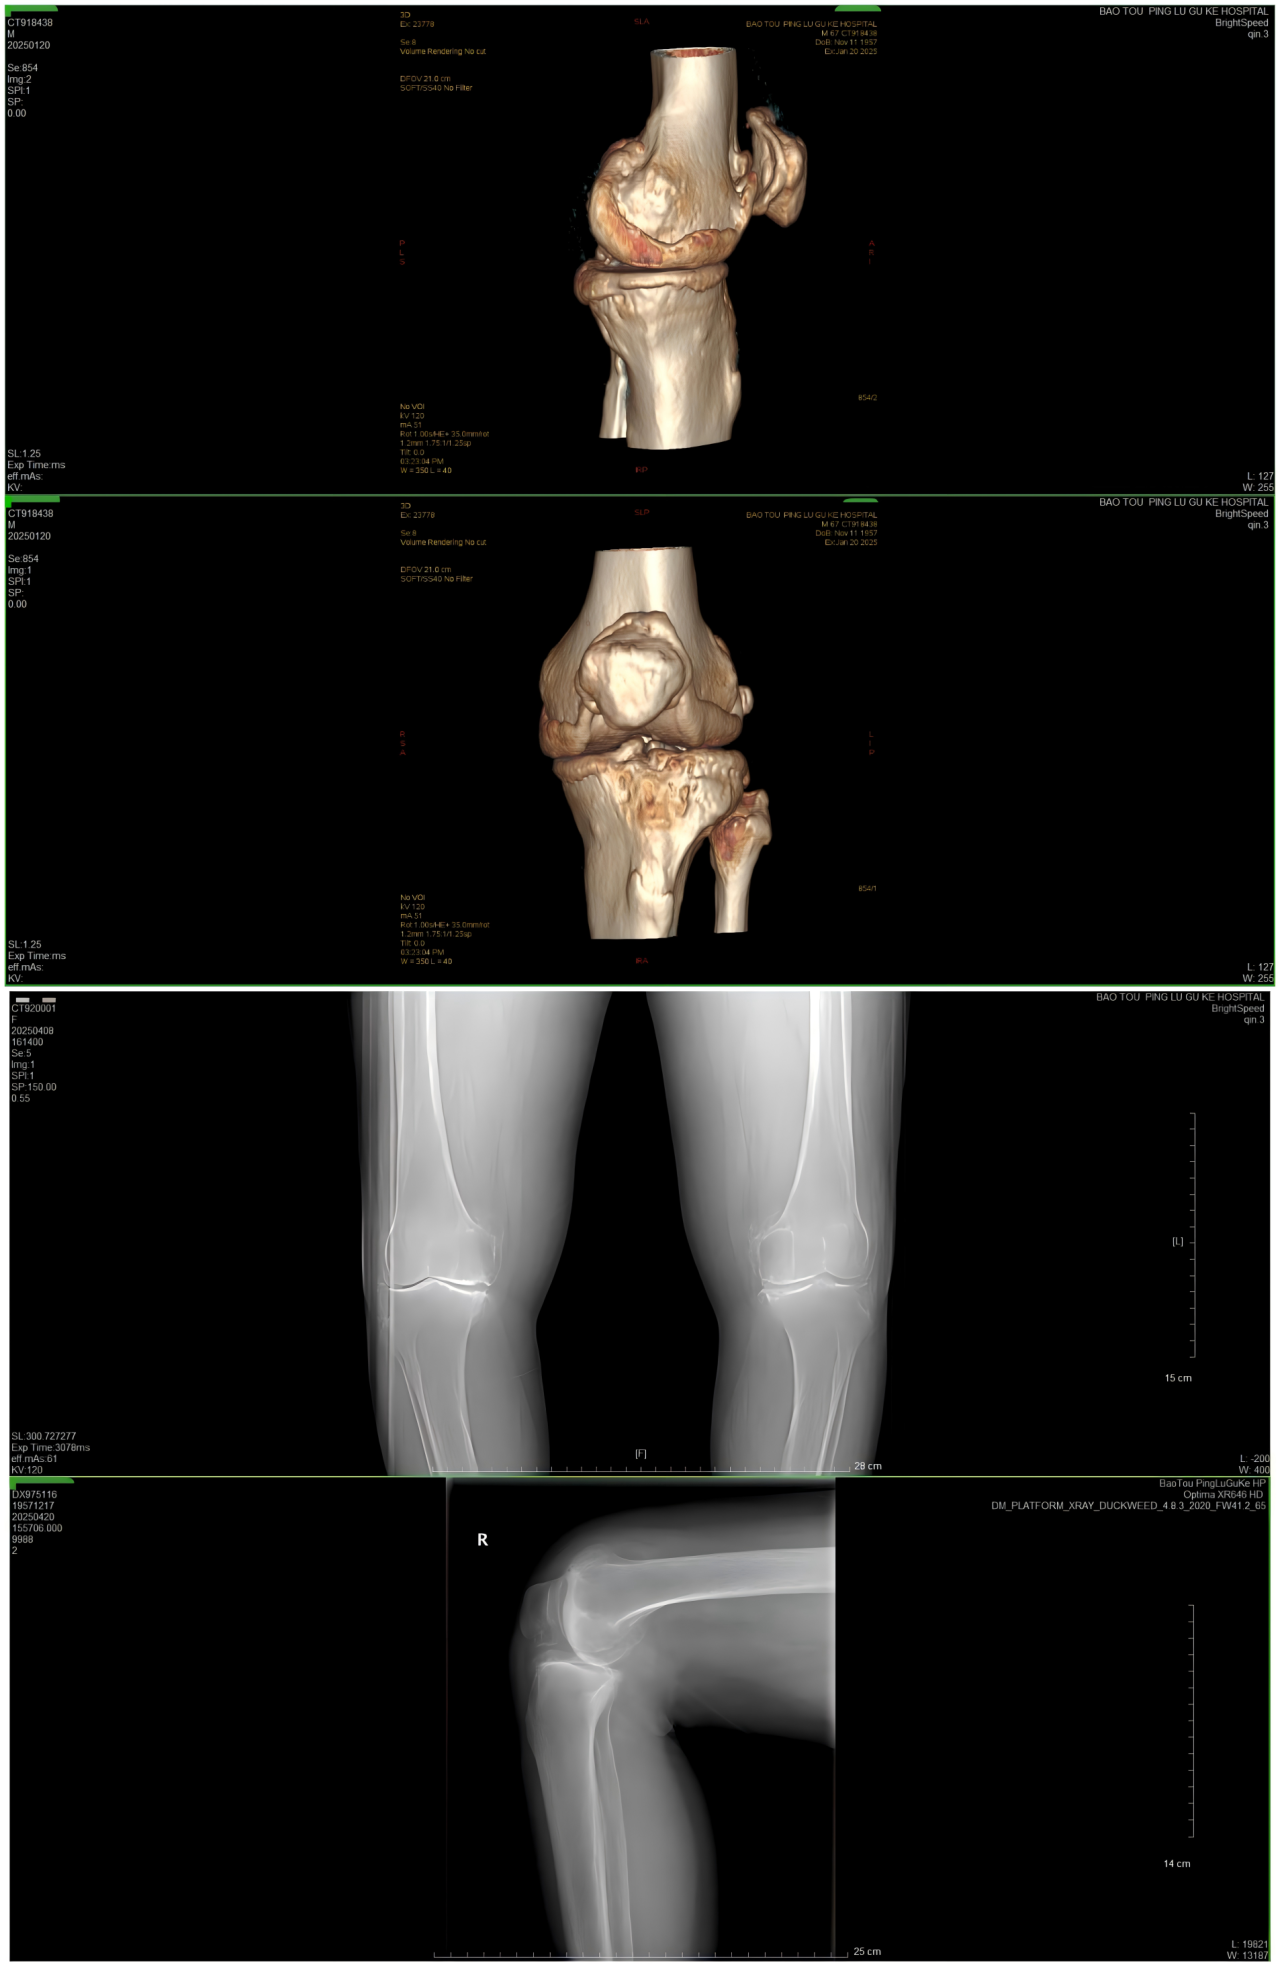

患者术后X光扫描

这个过程可以类比为镶牙,即切除受损部分并替换为金属材料。同理,在膝关节置换术中,医生会移除严重磨损的关节表面软骨及部分软骨下骨,在原位安装与原始膝关节表面形状类似的金属组件(即假体),使用骨水泥将假体与患者自身的股骨和胫骨固定在一起,使之恢复膝关节的正常功能。